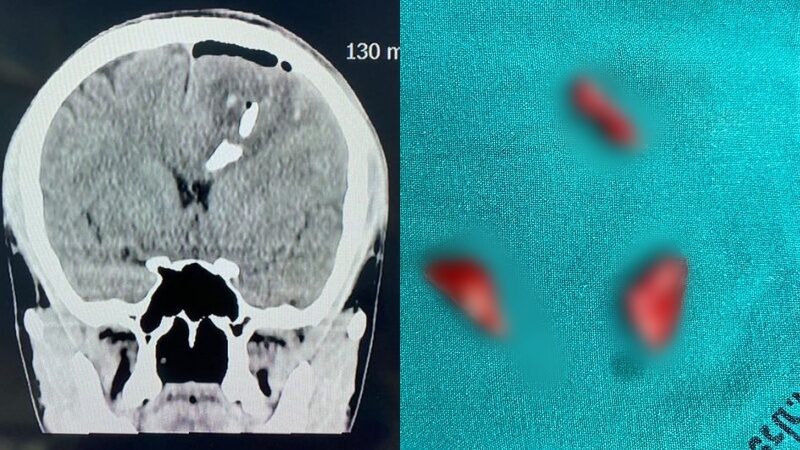

"กรณีตัวอย่างผู้ป่วยประสบอุบัติเหตุ ทางสมองอย่างรุนแรง ทำให้กะโหลกศีรษะแตกเป็นชิ้น ๆ ฝังลึกเข้าไปในเนื้อสมอง ทำให้มีภาวะเลือดออกในสมอง และเนื้อสมองถูกทำลายไปบางส่วน ผู้ป่วยยังรู้สึกตัว ถูกนำส่งโรงพยาบาลประจวบคีรีขันธ์"

"หลังจากดูแลเบื้องต้น เอกซเรย์สมอง ปรึกษาแพทย์ผู้เชี่ยวชาญด้านศัลยศาสตร์สมองและระบบประสาท เตรียมตัวผู้ป่วย นำเข้าห้องผ่าตัดทันที การผ่าตัดสมองค่อนข้างละเอียดอ่อน เพื่อหยุดเลือดที่ออก เอาเศษกระดูก กะโหลกศรีษะ ลิ่มเลือดที่ตกค้างออก เย็บปิดเยื่อหุ้มสมอง การผ่าตัดใช้เวลาประมาณ 1 ชั่วโมง ประสบผลสำเร็จเป็นอย่างดี ประเมินอาการทางสมองหลังผ่าตัดเป็นที่น่าพอใจ ขอให้ทุกท่านเดินทางปลอดภัย ในช่วงสงกรานต์นี้"